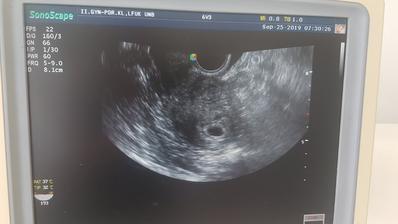

Zatial tajne dúfame,že všetko dobre dopadne..

...druhé šťastie...